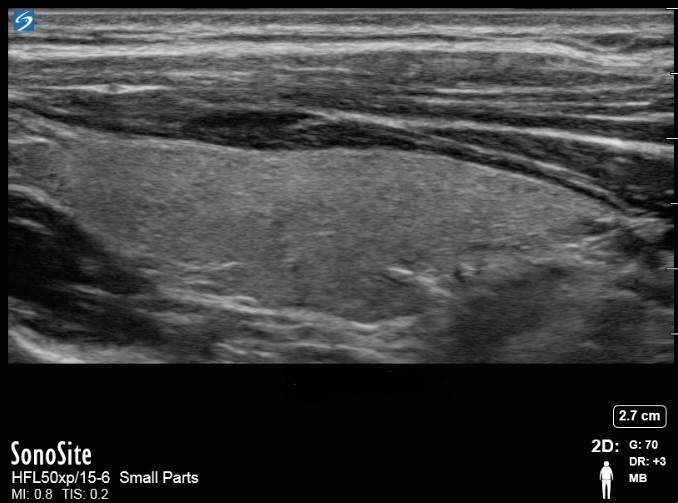

甲状腺矢状面图像